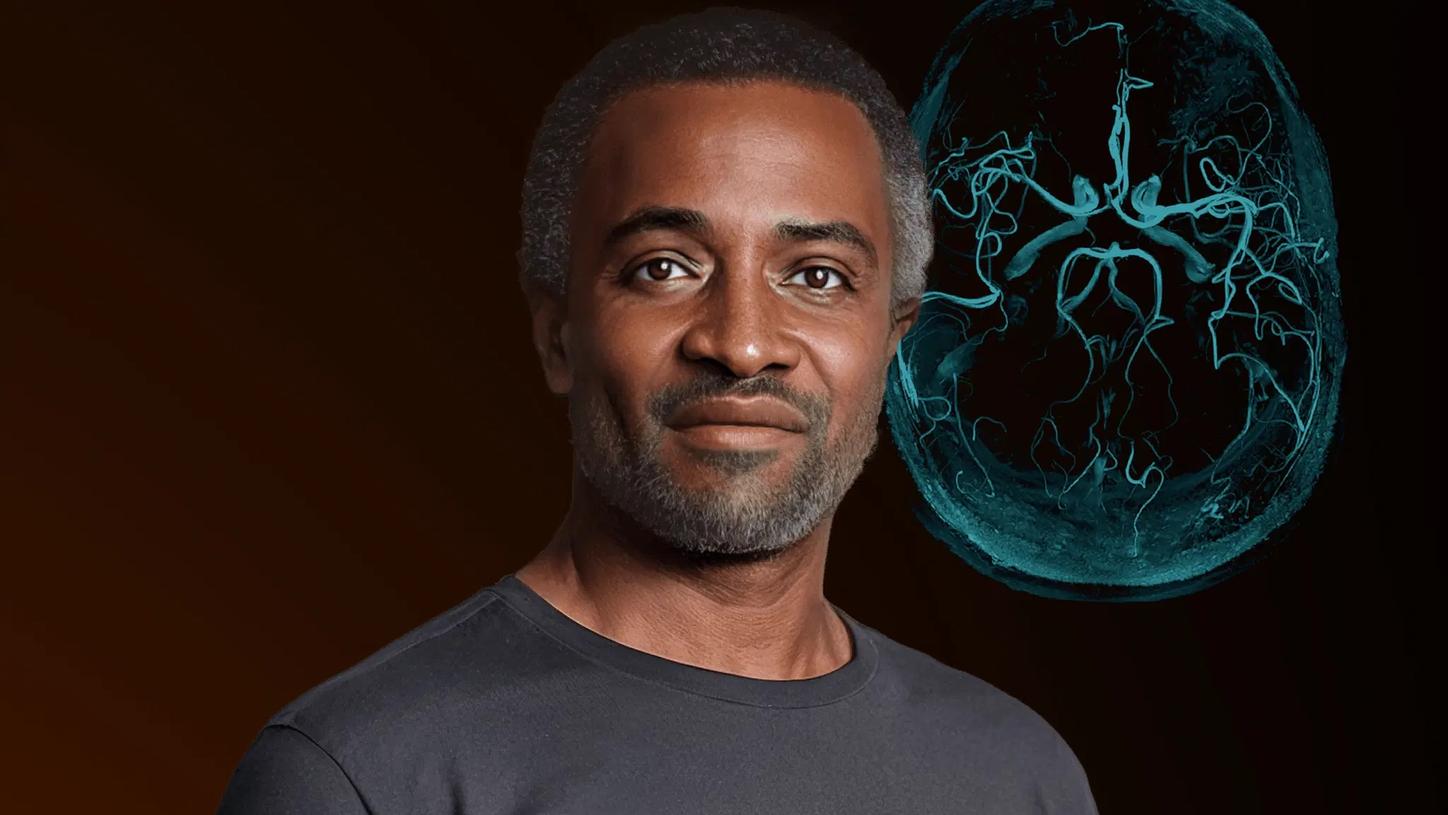

Follow Mike on his acute stroke health journey

Stroke is a medical emergency where every second matters. Rapid and precise diagnosis is critical for effective treatment and improved outcomes. Mike’s case (exemplary patient) illustrates what optimal stroke care can look like.